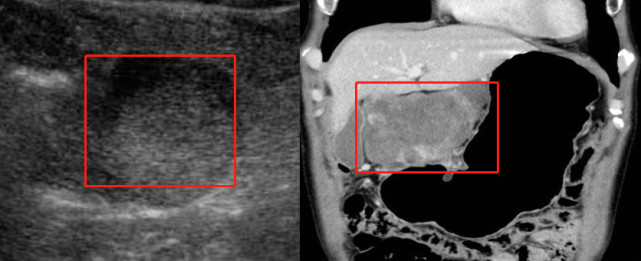

老杨,65岁,B超体检时发现肚子里长了一个肿块,直径已经达到10多厘米了。然后,医生建议他做CT。他就有疑问了,为什么已经做了B超,还要做CT?

图片(左图为B超结果,右图为CT结果,红色框区为肿块)

可以看到,CT对于肿块内部结构的显示比B超要清晰,而且能明显辨别周围的器官,更清楚地显示肿块范围及与周围脏器的关系。

那为什么不直接做CT,而是用B超做体检呢?

因为B超简便易行,无辐射损伤,安全、经济,适合作为初筛手段。如果发现有肿物了,再用CT去做进一步的检查,才是合理的搭配。